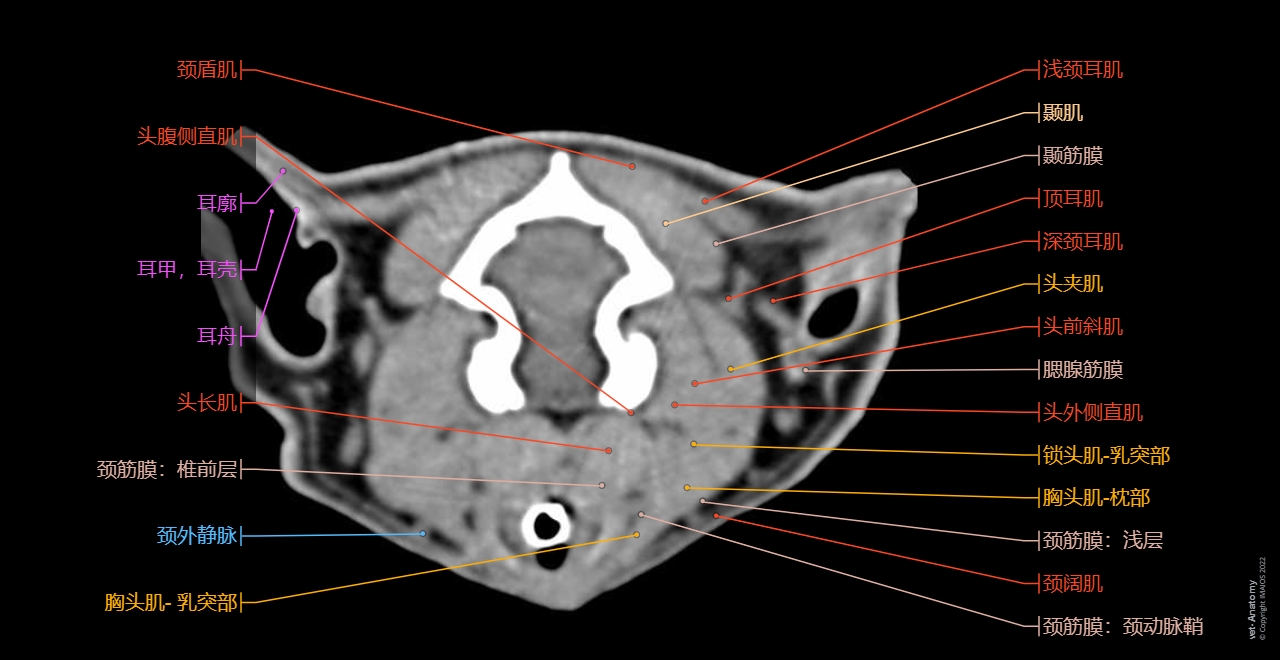

正常猫的头颈部CT解剖

- Antoine MICHEAU, MD , Denis HOA, MD , Susanne AEB Boroffka, PhD - dipl. ECVDI

- 发布日期: 2019年10月11日 | 最新更新 2025年3月18日